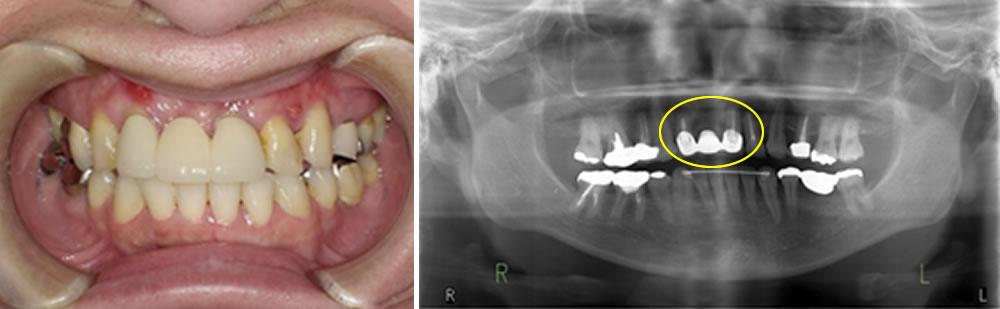

こちらの患者さまは、元々、右上2から左上1にかけて(右上1欠損部)のブリッジが装着されていました。支台歯はいずれも神経を除去し、根管治療が行われている歯でしたが、歯質の残存量や状態から予後はあまり良好とはいえない状況でした。

長期的な維持は難しいと判断し、今後の治療方針についてご説明した結果、インプラント治療を選択することになりました。